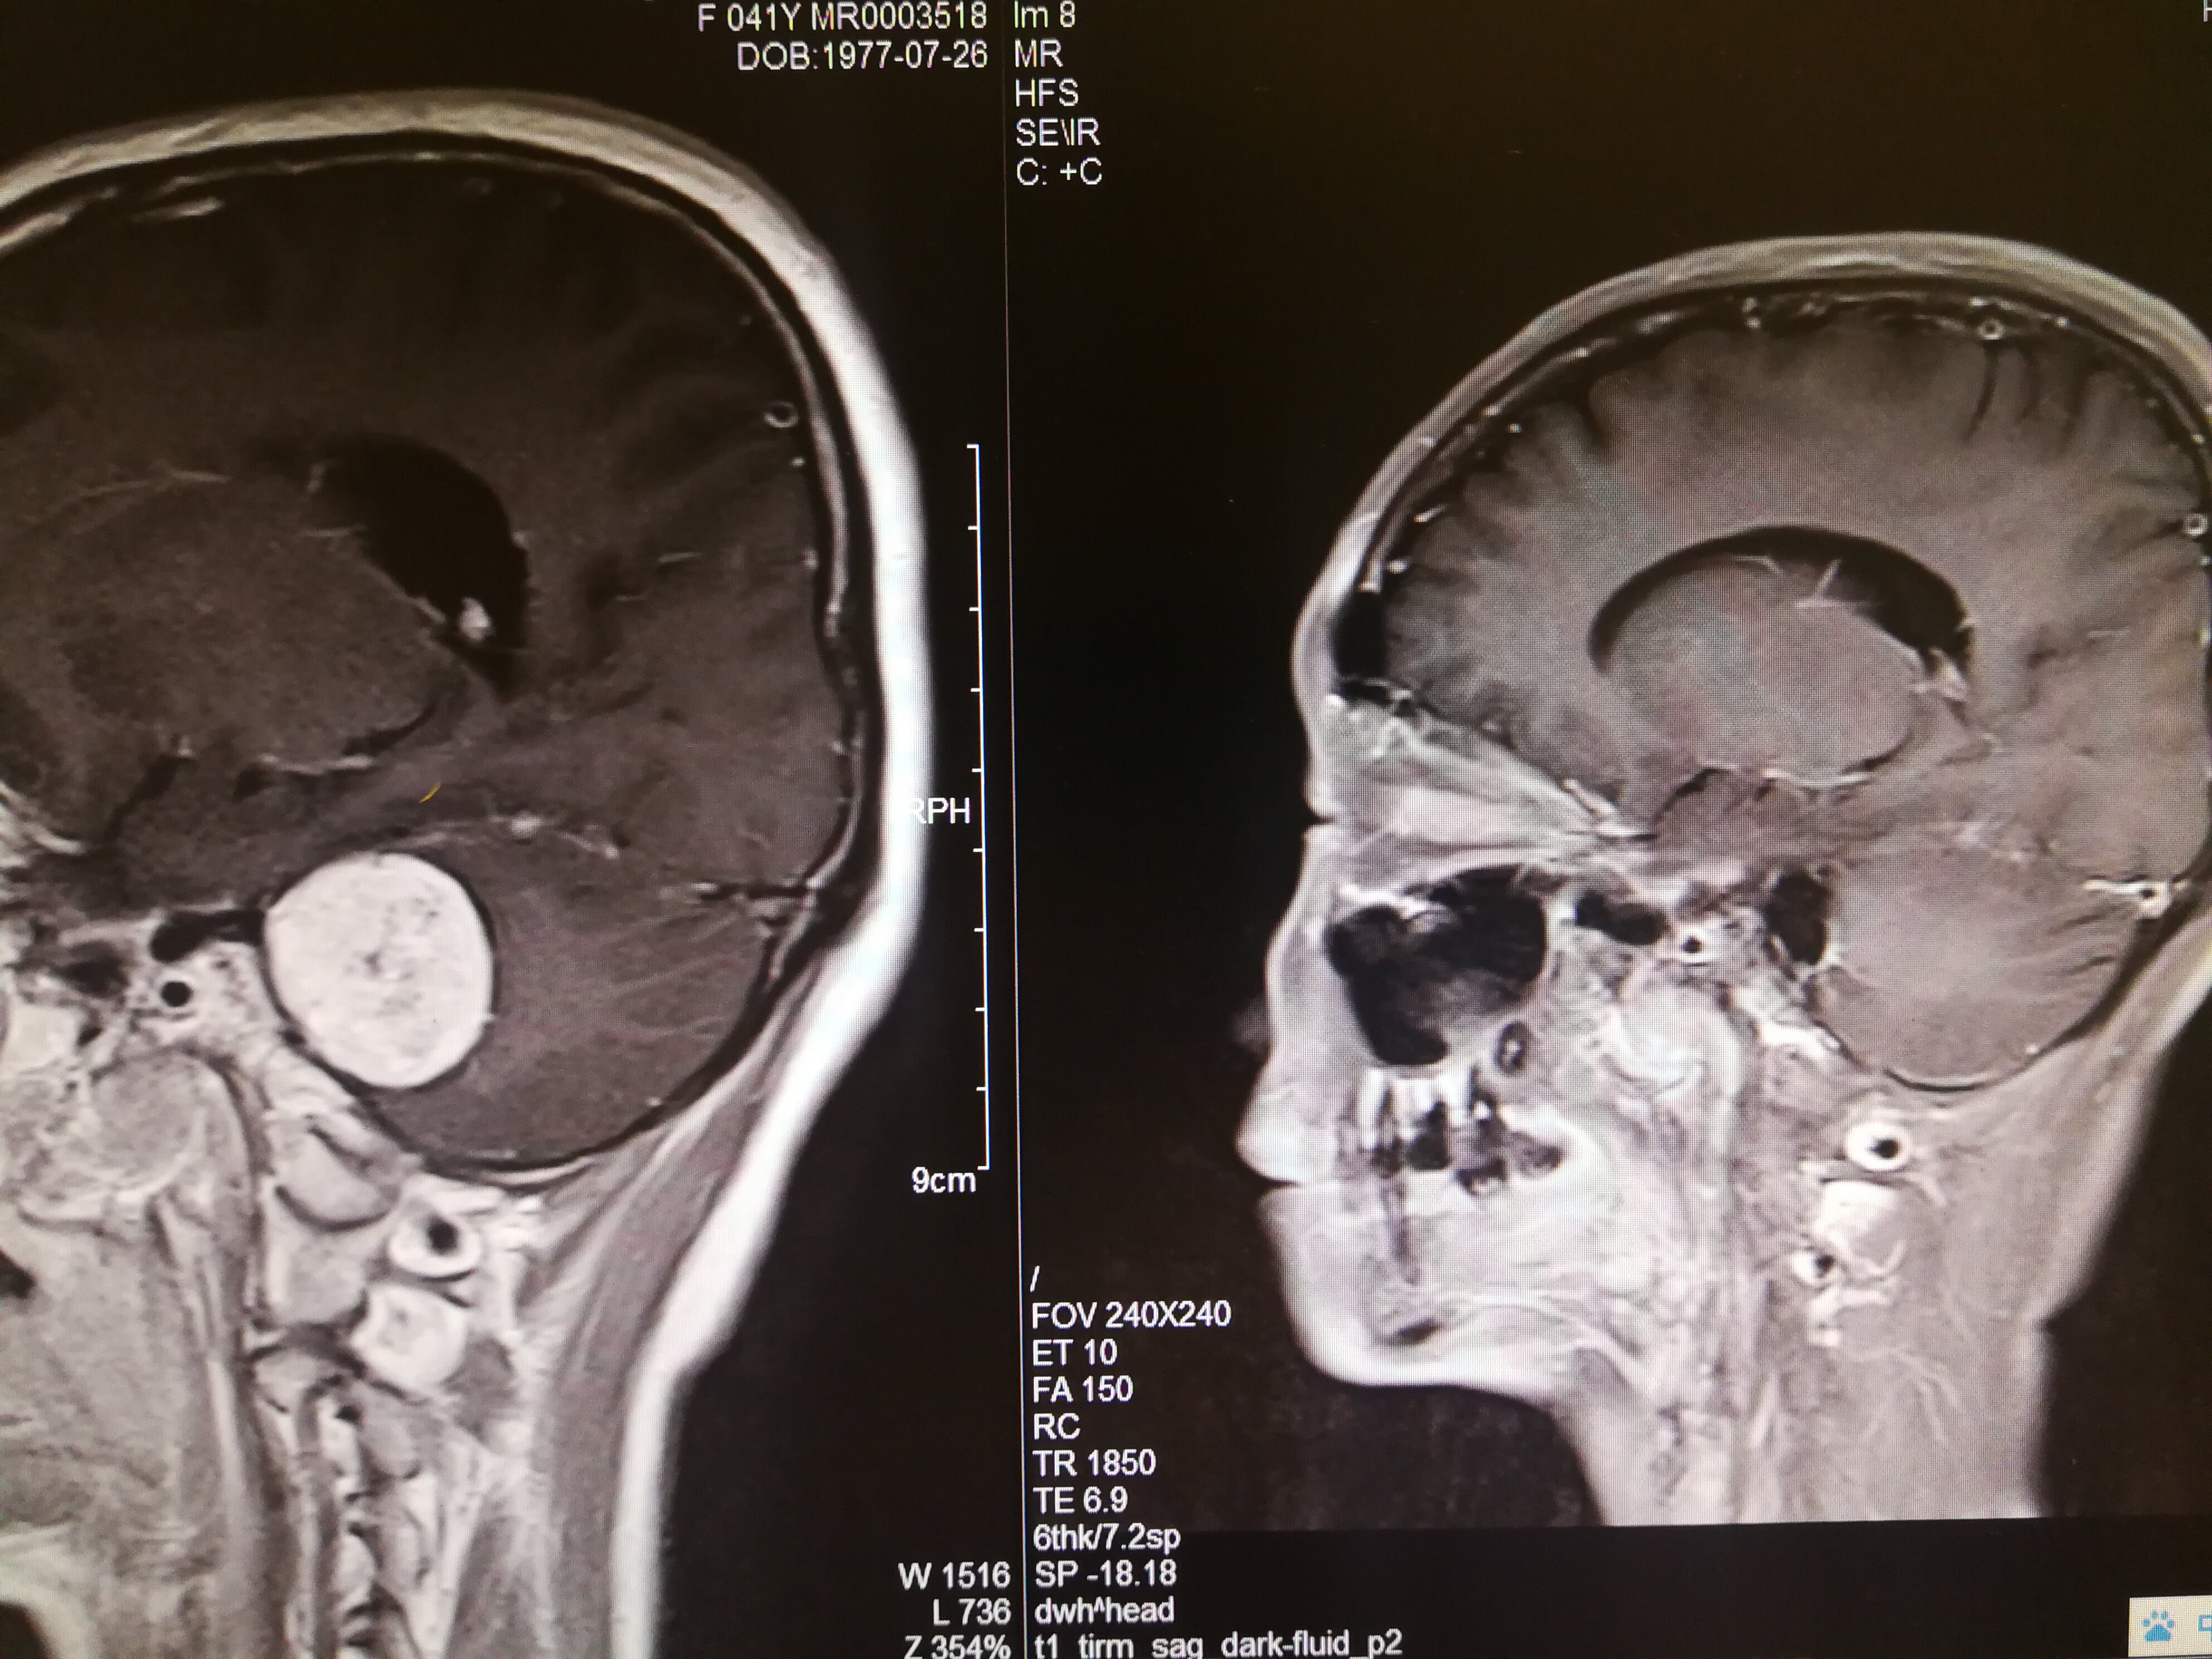

手术治疗听神经瘤是最主要的治疗方式,目前听神经瘤的手术已经非常成熟,只要没有明显的手术禁忌症首先应考虑手术治疗,并要求在电生理监测条件下完成手术,这样可以最大限度地保护面神经功能。以下是几例我们做的听神经鞘瘤手术前后核磁共振片子对照,除手术后听力不能恢复外,没有面瘫,脸部麻木,吞咽困难等颅神经症状,也无其他较明显的手术并发症发生。